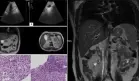

Figura 1. La tomografía computarizada reveló una masa adyacente al colon descendente con realce periférico dependiente de la pared colónica, que se extendía hacia la capa muscular, sugestivo de un absceso, así como un pequeño objeto radiopaco en el medio del flemón, que apoyaba un cuerpo extraño.

La tomografía computarizada abdominal y pélvica con contraste reveló la presencia de una masa adyacente al colon descendente con realce periférico dependiente de la pared colónica, que se extendía hacia la capa muscular, sugiriendo un absceso.

Además, se identificó un pequeño objeto radiopaco en medio del flemón, compatible con un cuerpo extraño penetrante. Esto, junto con la acumulación de grasa pericólica y líquido libre en la fosa ilíaca izquierda, orientaron inicialmente hacia un proceso neoplásico complicado o un absceso de origen diverticular, aunque la presencia del cuerpo extraño añadió una etiología inusual al cuadro.